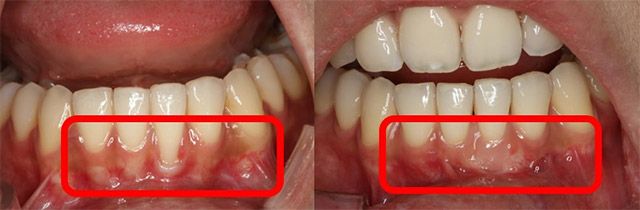

치은퇴축의 치료법으로는 퇴축된 부위 아래 및 측면부 잇몸을 이동시키는 잇몸 성형술과 잇몸 이식술 등이 있다. 잇몸 이식술은 구개(입천장) 측에서 충분한 양의 결합조직 이식 편을 채취해 퇴축 부위에 덮는 방식으로 진행한다. 치료를 통해 노출된 치아 뿌리를 덮고 잇몸의 높이와 부피를 회복할 수 있다. 이에 앞서, 치주질환으로 인해 전반적인 치조골 소실과 치은퇴축 양상이 관찰되는 경우에는 철저한 치주치료로 더 이상의 퇴축을 방지하는 것이 필수적이다.